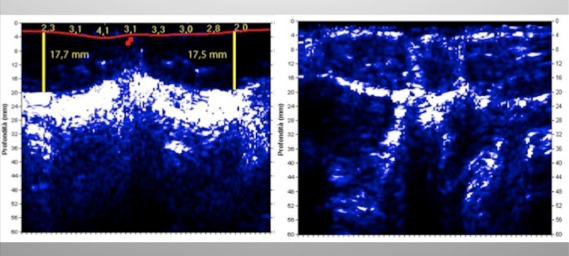

L’ecografo infatti consente di valutare con estrema precisione lo spessore degli strati adiposi localizzati e lo stato dei muscoli sottostanti!

Non solo fornisce quindi informazioni sempre più precise su la composizione corporea ma consente anche di monitorare i progressi fatti dall’allenamento, infatti questo strumento fornisce un’immagine dettagliata della struttura muscolare, permettendo al professionista di verificare la conicità del muscolo, la sua atrofia o la presenza di infiltrazioni di grasso indicando quindi un muscolo di bassa qualità.